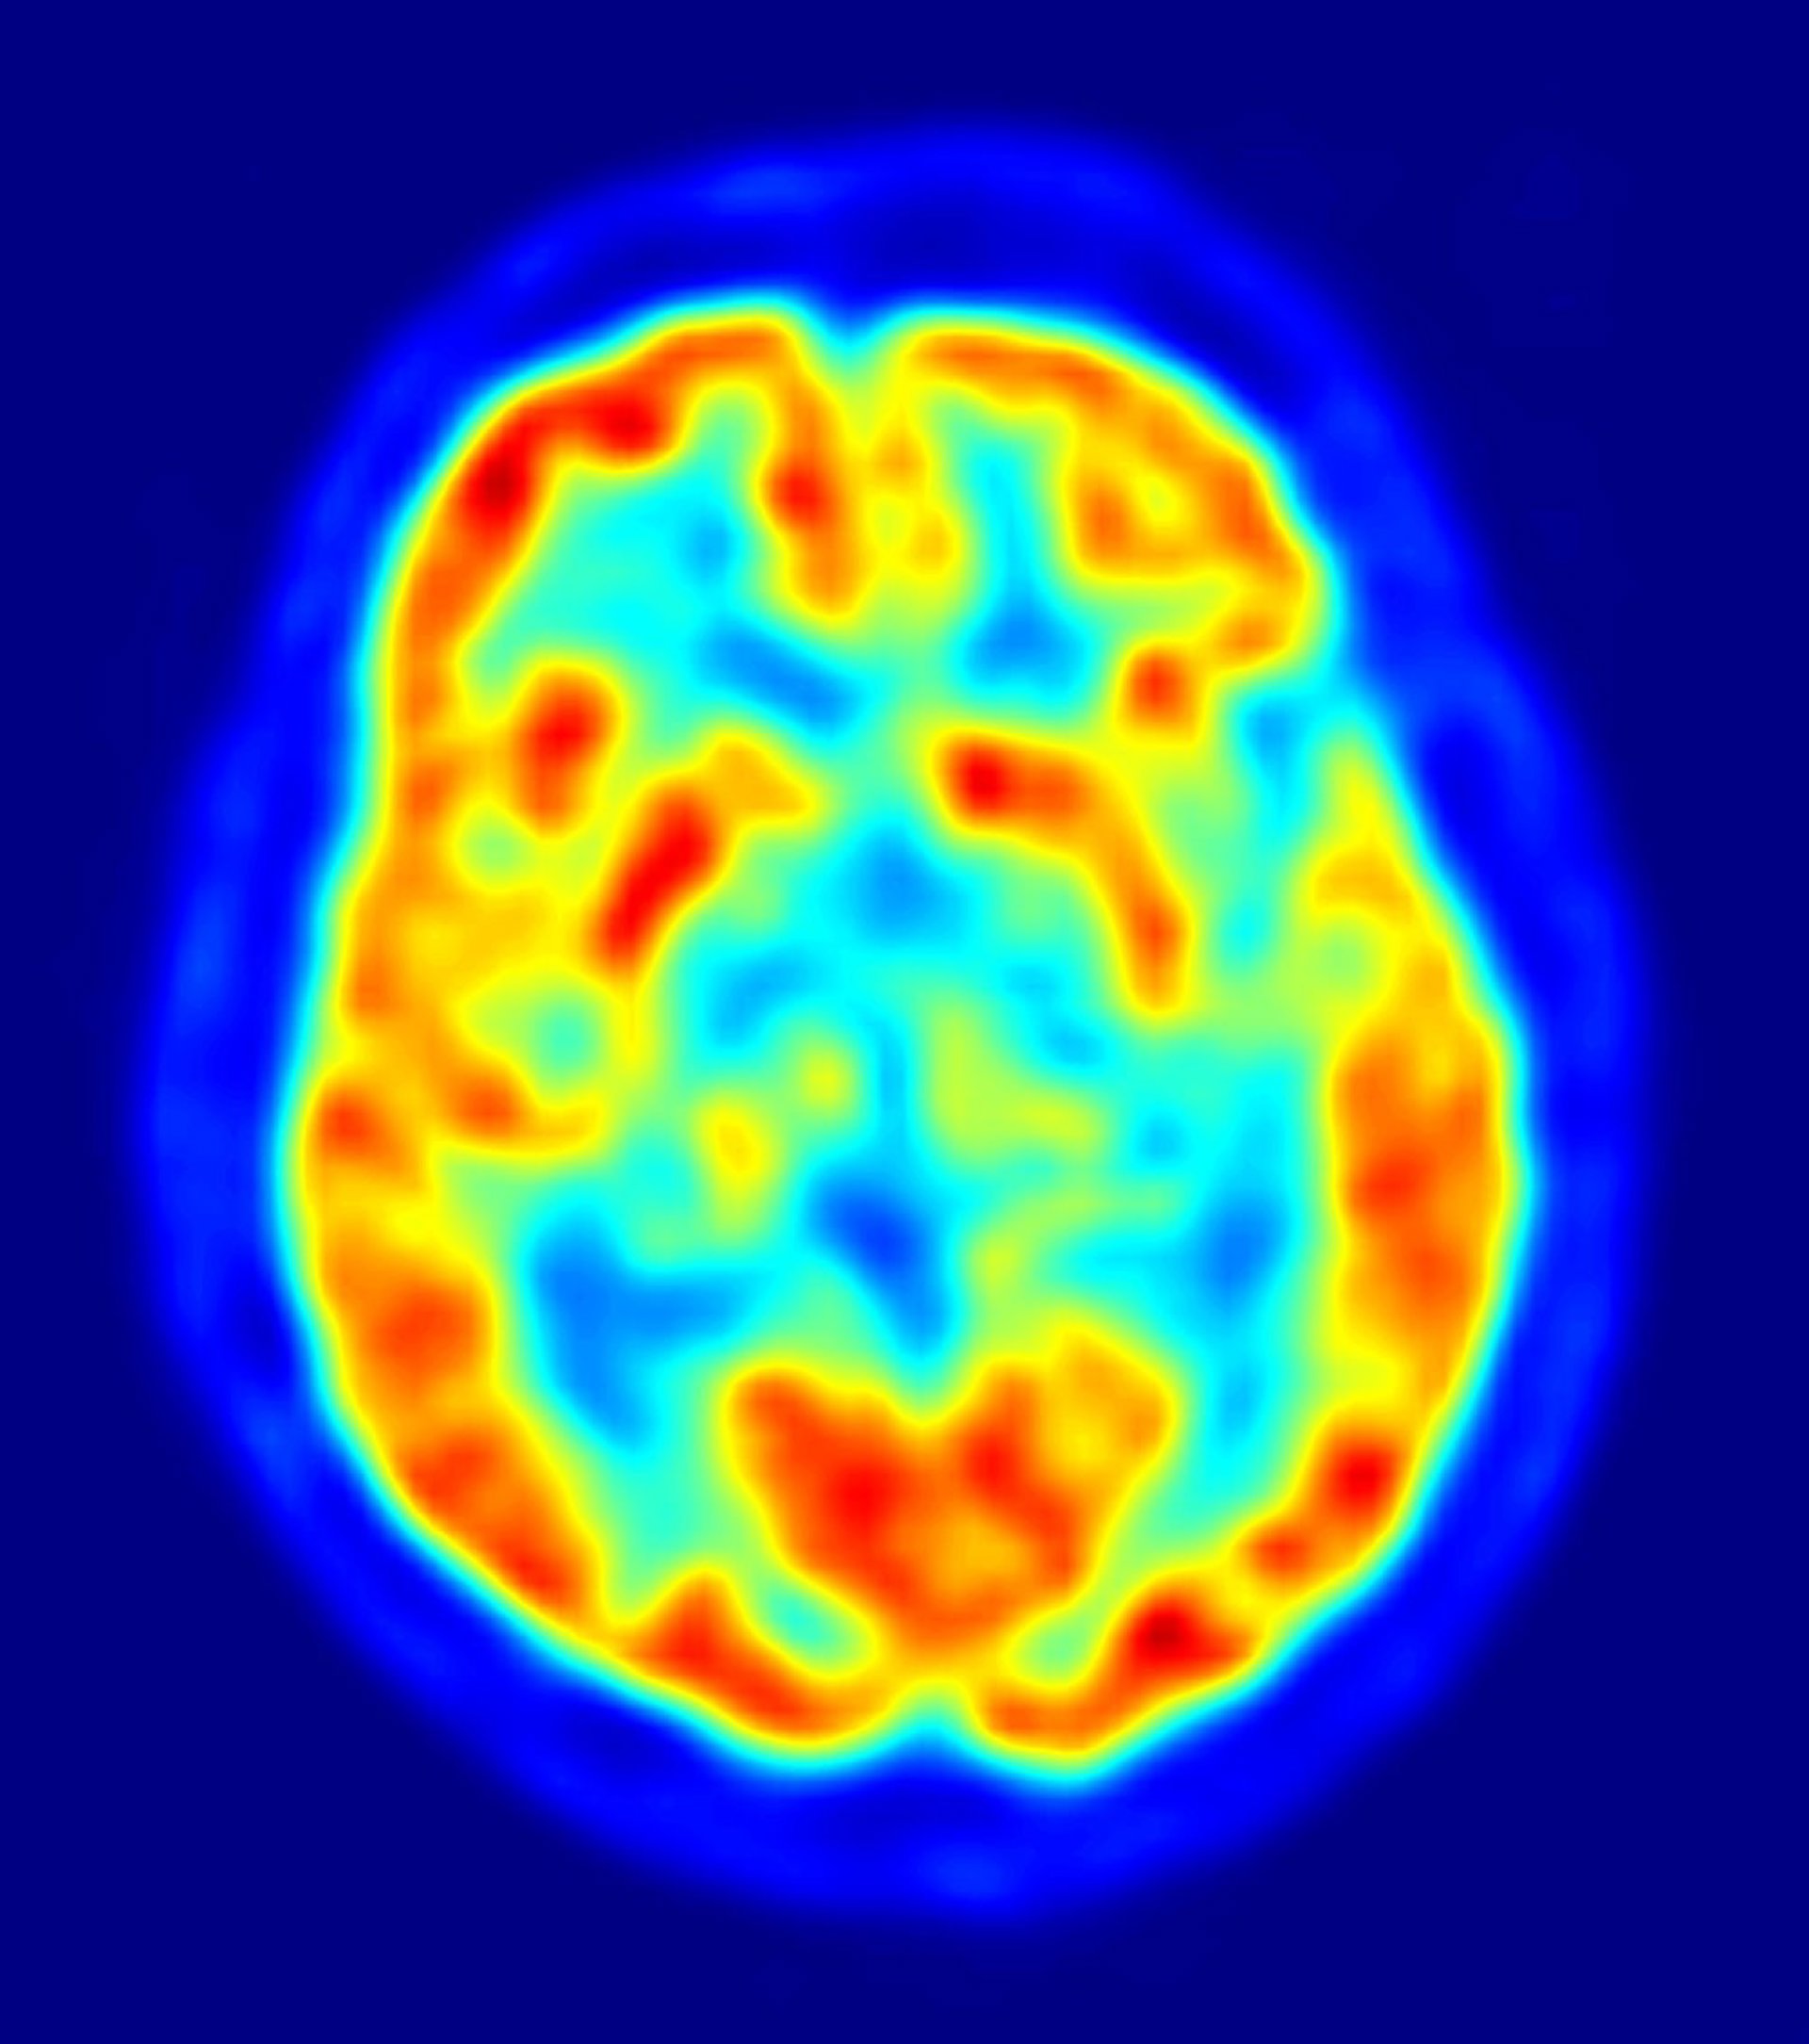

El tratamiento con metadona puede afectar a las células nerviosas del cerebro a largo plazo, según ha mostrado un reciente estudio del Instituto Noruego de Salud Pública. De esta forma, este trabajo continúa la senda de otros anteriores que consideraban que esta droga "afectan al funcionamiento cognitivo".

En este sentido, los expertos confirman que capacidades como el aprendizaje y la memoria pueden verse perjudicadas. Para ello, y dada la imposibilidad de llevar a cabo estudios controlados en pacientes con metadona, los investigadores emplearon ratas durante los ensayos clínicos.

En los mismos, los animales recibieron una dosis diaria de metadona durante tres semanas, tras las que se les extrajo las áreas del cerebro donde se ubican el aprendizaje y la memoria. Al analizar los posibles cambios o daños neurobiológicos establecidos, los expertos descubrieron que se originó una reducción del 70 por ciento en una molécula importante en estas capacidades.

Tras producirse este efecto, tanto en el hipocampo como en la parte frontal del cerebro, los científicos también observaron que esta circunstancia se mantenía una vez eliminada la droga del organismo, lo que "puede ser motivo de preocupación", señalan. No obstante, un estudio paralelo de la Universidad Southwestern de Texas (Estados Unidos) ha concluido que la metadona no tiene incidencia en la generación de nuevas células nerviosas.